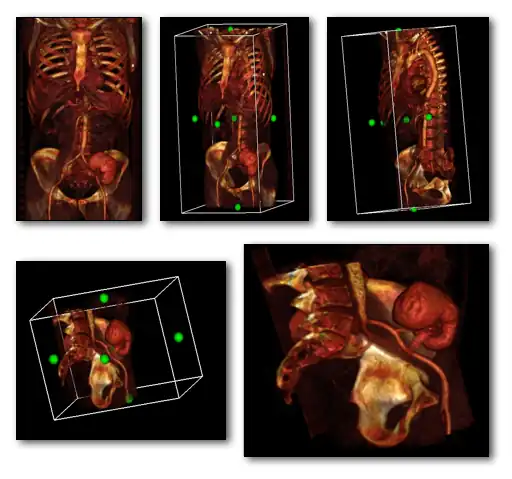

A final feature to note about volume rendering is that 3D editing techniques can be applied so as to exclude unwanted features from the computations and to expose internal structure. This is illustrated in the following figure, where planes of an orthogonal frame can be moved to crop the voxel data from six directions.